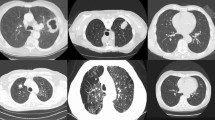

One of the dreadful diseases in the medical industry is prostate cancer and it is growing at a higher rate among men. Hence, it is a necessity to detect cancer in an early stage due to the alarming increase in the reports. Various techniques are introduced for effective prostate cancer detection using histopathology images. Accordingly, an automatic method is proposed for segmenting and classifying prostate cancer. This paper presents the prostate cancer detection method using histopathology images by proposing the fuzzy-based salp swarm algorithm-based rider neural network (SSA-RideNN) classifier. At first, the input image is fed to the pre-processing step and then the segmentation is performed using Color Space transformation and thresholding. Once the segmentation is performed, the feature extraction is done by extracting multiple kernel scale invariant feature transform features along with the texture features that are extracted based on local optimal oriented pattern descriptor to improve the classification accuracy. Finally, the prostate cancer detection is done based on the proposed fuzzy-based SSA-RideNN, which is developed by integrating fuzzy approach with SSA-RideNN. The performance of the proposed fuzzy-based SSA-RideNN is analyzed using sensitivity, specificity, and accuracy. The proposed fuzzy-based SSA-RideNN produces the maximum accuracy of 0.9190, a maximum sensitivity of 0.9084, and maximum specificity of 0.9, indicating its superiority.

Roy S, Kumar Jain A, Lal S, Kini J (2018) A study about color normalization methods for histopathology images. Micron 114:42–61

National Cancer Institute GDC Data portal. https://portal.gdc.cancer.gov/annotations. Accessed on Nov 2018